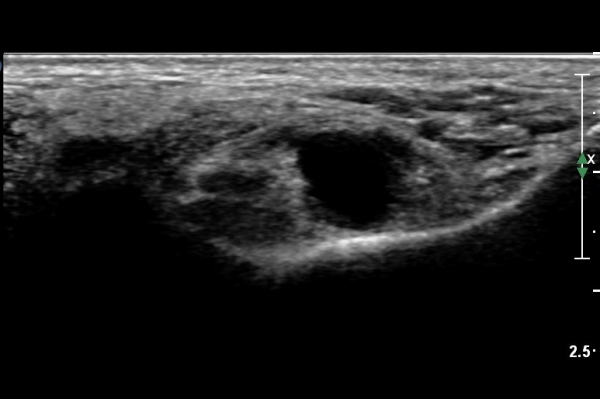

ŽÃËÀÚ¸¦ Á¶±Ý ´õ À̵¿ÇÏ´Ï ³¶Á¾ÀÌ ¿ÜÃøÁ·Àú½Å°æ Ç¥ÃþÀ¸·Î À§Ä¡ÇÑ´Ù. ½Å°æÀÇ ½ÉÃþ¿¡¼­´Â

±ä¾öÁö±¼°î°ÇÀÌ º¸ÀδÙ(»çÁø 4, 5).

ŽÃËÀÚ¸¦ Á¶±Ý ´õ À̵¿ÇÏ´Ï ³¶Á¾ÀÌ Ä¿Áö¸é¼­ ¿ÜÃøÁ·Àú½Å°æÀ» ¾Ð¹ÚÇÏ´Â °ÍÀÌ ¶Ñ·ÈÇÏ´Ù(»çÁø 6, 7, 8, 9).

¿ÜÃøÁ·Àú½Å°æÀ» Á¾´Ü¸éÀ¸·Î °üÂûÇÏ´Ï ½Å°æÀÇ ÁÖÇàÁß¿¡ ³¶Á¾¿¡ ÀÇÇÑ ¾Ð¹ÚÀÌ ¶Ñ·ÈÈ÷ °üÂûµÈ´Ù(»çÁø 10).